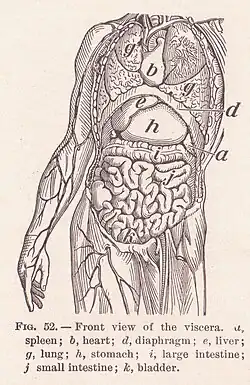

Viscera

In the study of anatomy, viscera (sg.: viscus) refers to the internal organs of the abdominal, thoracic, and pelvic cavities.[5] The abdominal organs may be classified as solid organs or hollow organs. The solid organs are the liver, pancreas, spleen, kidneys, and adrenal glands. The hollow organs of the abdomen are the stomach, intestines, gallbladder, bladder, and rectum.[6] In the thoracic cavity, the heart is a hollow, muscular organ.[7] Splanchnology is the study of the viscera.[8] The term "visceral" is contrasted with the term "parietal", meaning "of or relating to the wall of a body part, organ or cavity".[9] The two terms are often used in describing a membrane or piece of connective tissue, referring to the opposing sides.[10]

The adjective visceral, also splanchnic, is used for anything pertaining to the internal organs. Historically, viscera of animals were examined by Roman pagan priests like the haruspices or the augurs in order to divine the future by their shape, dimensions or other factors.[19] This practice remains an important ritual in some remote, tribal societies.

The term "visceral" is contrasted with the term "parietal", meaning "of or relating to the wall of a body part, organ or cavity"[9] The two terms are often used in describing a membrane or piece of connective tissue, referring to the opposing sides.[20]